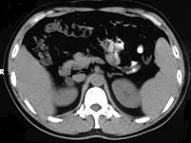

问题 女,23岁,满月脸、向心性肥胖,CT扫描如图所示,应诊断为 ( )

选项 A、右侧肾上腺嗜铬细胞瘤 B、右侧肾上腺转移瘤 C、右侧肾上腺腺瘤 D、右侧肾上腺腺癌 E、右侧肾上腺增生

答案 C